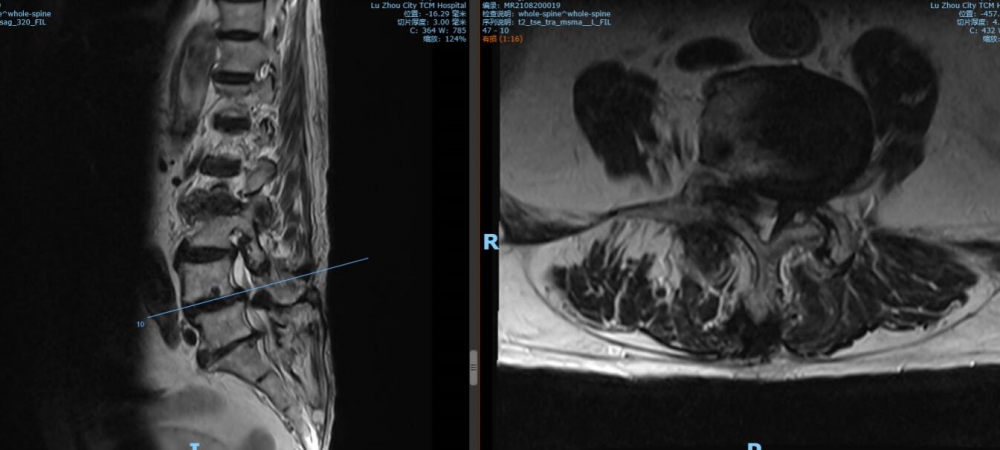

腰4 5椎间盘CT

腰4 5椎间盘MRI

泸州市中医医院骨伤二科主治中医师胡建超介绍,李谨行老人患有腰椎管狭窄症 、腰4椎I°滑脱 、脊柱退行性侧弯畸形 、冠状动脉粥样硬化性心脏病、心律失常、高血压2级等17种疾病,同时处于慢性阻塞性肺病加重期和脑梗塞恢复期。92岁、全身多种疾病,随时可能会有突发情况,要做这样一个大手术,对医生和患者来说,无疑都是一个巨大的挑战。